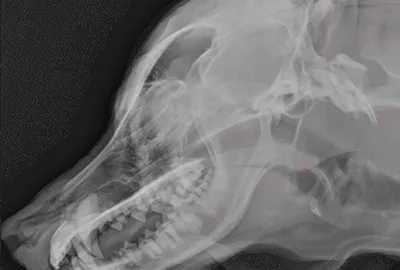

Rentgen (RTG)

Rentgen se používá hlavně k zobrazení kostí a jejich poškození, například při podezření na zlomeninu, vykloubení nebo jiné úrazy hlavy. Výhodou je, že je dostupný téměř na každé veterinární klinice, je levný a rychlý. Nevýhodou je, že špatně zobrazuje měkké tkáně a někdy je nutné zvíře složitě polohovat, což může ovlivnit kvalitu snímků.